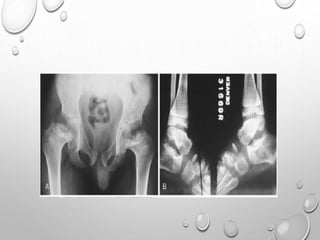

EPIPHYSEAL DYSPLASIA

MULTIPLEX

AD TRANSMISSION

EQUAL IN MALES AND FEMALES

FIRST NOTICED WHEN CHILD BEGINS TO WALK , WITH COMMON

COMPLAINTS OF WADDLING GAIT , DIFFICULTY RUNNING.

MILDER CASES MAY NOT APPARENT UNTIL EARLY ADULTHOOD ,

WHEN PREMATURE JOINT DEGENERATIVE CHANGES OCCURS.

PATHOPHYSIOLOGY : ABNORMALITY OF EPIPHYSEAL

CHONDROCYTES ( NO DECREASED , ABNORMAL ARRANGEMENT

)….LEADING TO DELAYED AND DISORDERLY OSSIFICATION F

EPIPHYSES.

LL >> UL

SHORT STATURE WITH TENDENCY TOWARDS DWARFISM

BILATERAL SYMMETRICAL INVOLVEMENT

DEVELOPMENT OF EPIPHYSES DELAYED

APPEARANCE IS MOTTLED WITH IRREGULAR MINERALIZATION

FLATTENED AND SQUARED-OFF EPIPHYSES

DOUBLE LAYERED PATELLA……PATHOGNMONIC

HYPOPLASTIC TIBIAL AND FEMORAL CONDYLES WITH SHALLOW

INTERCONDYLAR NOTCH

METAPHYSES ARE FLARED

CARPALS , TARSALS AND LONG TUBULAR BONES OF HAND ,SOMETIMES

FEET ARE SHORT AND THICK

SPINE : ANTERIOR WEDGING , SCOLIOSIS

IRREGULAR EPIPHYSES LEADS TO PREMATURE AND SEVERE

DEGENERATIVE CHANGE ESPECIALLY IN KNEES AND HIPS.